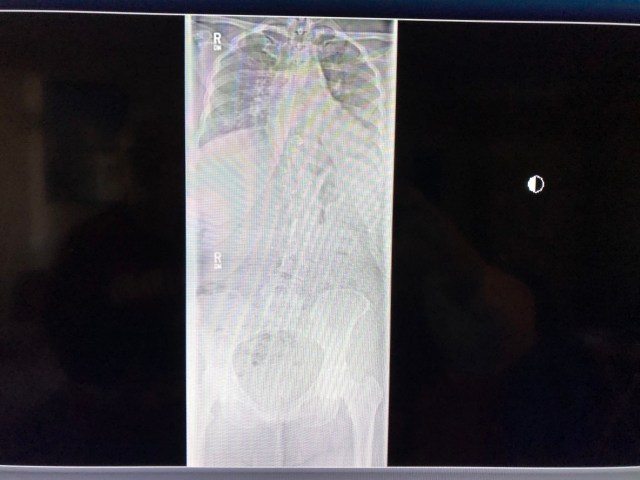

The most problematic issue has been my spine. I have scoliosis and it has gotten markedly worse over the past few years while working as a professional driver.

Here are some recent x-rays of my back: